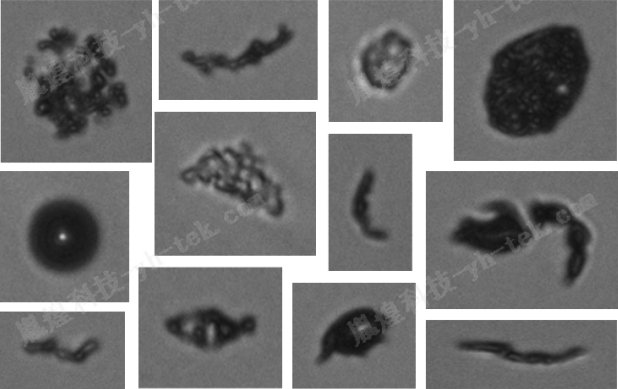

微流成像顆粒分析系統基于微流技術和光學成像原理,通過高精度的高速攝影儀對流經微流通道的樣品進行實時拍攝和數據采集。該系統能夠實現對顆粒粒度、濃度及形狀特點的精確測量,為蛋白制劑的研發和質量控制提供有力支持。

高效的數據處理能力:采用先進的圖像處理算法,系統能夠自動識別和分割圖像中的顆粒,并提取出每個顆粒的粒度、形狀等關鍵信息。

直觀的數據分析:處理后的數據以可視化的形式展示,用戶可以輕松查看顆粒的粒度分布曲線、形態圖像以及統計分析結果。